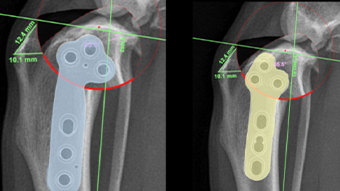

V-pop 프로그램을 이용한

세심한 수술 계획,

수술 중 발생할 수 있는 변수 조절

예은동물의료센터는 V-pop 프로그램을 이용하여 세심한 수술 계획을 세우고 수술 중 발생할 수 있는 변수 조절합니다.

또한 다양한 정형외과 회사 제품 보유로 환자 맞춤 수술 가능합니다.

다양한 크기/다양한 뼈 모양에 가능한 기구 보유하여 리허설을 통해서 환자에게 가장 적합한 플레이트 이용합니다.

십자인대 질환

- TPLO

- 9살, 11kg, 아메리칸코커스패니엘

십자인대 질환에 대해 TPLO 수술을 진행하였습니다. 수술 직후 방사선에서 절골선이 보이지 않습니다.

정교하고 안정적인 수술로 다음날부터 산책이 가능합니다.

십자인대 질환

- 5 hole TPLO

- 11살 3kg 말티즈

다양한 회사의 플레이트 제품을 가지고 있어서 환자 맞춤으로 수술이 가능합니다.

일반적으로 TPLO 수술 시 6홀 플레이트를 사용하는데

이 환자의 경우 뼈가 작아 5홀 플레이트를 사용하여 교정하였습니다.